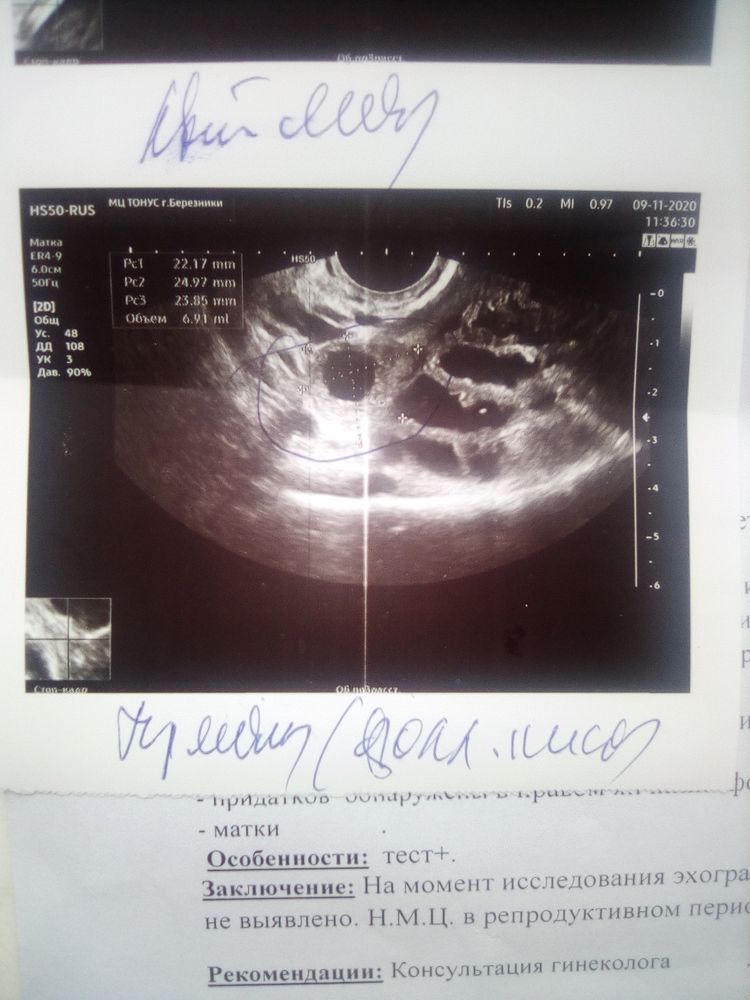

Сдайте ХГЧ в динамике 2 раза, через 48 часов. Если будет расти, и больше 1500, то идите снова на УЗИ - уже увидят ПЯ. А вообще, странно, что не увидели желтое тело, и эндометрий 7 мм - это "небеременный" эндометрий. А когда у Вас последние месячные были?

Julia Tim, во время были с 9 октября по 12 октября

Размер матки не беременный совсем.

тест на берменность ХГЧ 3000 на УЗИ нет беременности